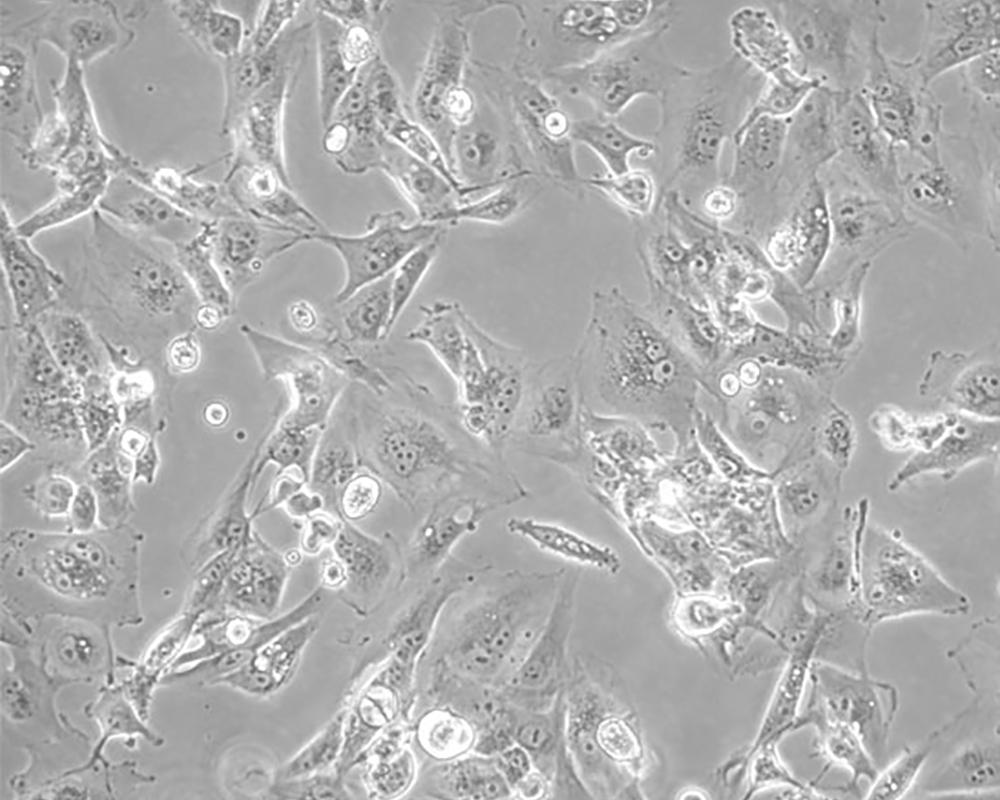

Caki-1

產(chǎn)品名稱 Caki-1

中文名稱 人腎透明細(xì)胞癌皮膚轉(zhuǎn)移細(xì)胞

組織來(lái)源 腎透明細(xì)胞癌;皮膚轉(zhuǎn)移;男性

生長(zhǎng)特性 adherent

形態(tài)特征 epithelial

細(xì)胞描述 該細(xì)胞超微結(jié)構(gòu)中包含許多微絨毛、少許微絲、許多小線粒體、發(fā)達(dá)的高爾基休和內(nèi)質(zhì)網(wǎng)、許多脂滴和多層體、次級(jí)溶酶體,沒有發(fā)現(xiàn)病毒顆粒。